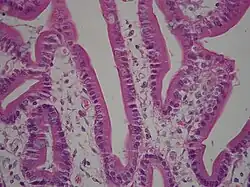

Transport Epithelia

These epithelia are found lining the tubes of the intestine and the kidney.

- The cells are usually columnar and regulate the exchange of nutrients an ions.

- The apical surface usually has microvilli, fingerlike projections that can increase the absorptive area up to 100X.

- These cells are usually bound together with tight junctions

- These cells usually have a high metabolism (numerous mitochondria)